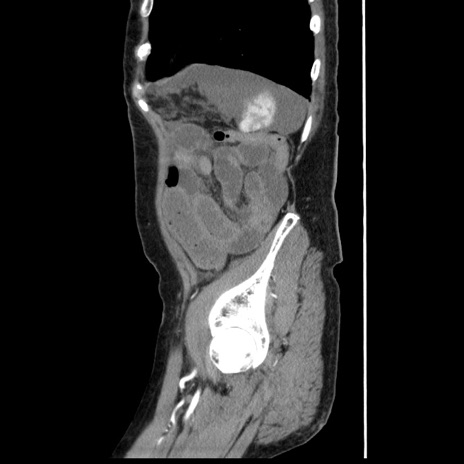

症例1(矢状断像)

【症例】80歳代女性

【主訴】腹痛

【現病歴】8時間前から腹痛あり来院。

【既往歴】糖尿病、脂質異常症、子宮体癌にて子宮全摘術

【身体所見】意識清明・会話良好だが腹痛で苦悶様、全腹部にわたって反跳痛と圧痛あり

【データ】WBC 13600、CRP 0.14、LDH 224、CK 90